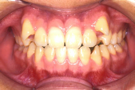

治療前

治療後

かみ合わせの高さ(咬合高径)を維持するため、あえて小臼歯も知歯も抜歯していません。

①主訴 前歯の前突 ②診断名 上顎前突 ③年齢 18歳 ④使用装置 エッジワイズ装置 ⑤抜歯部位 なし ⑥治療期間 約2年 ⑦治療費概算 90万円